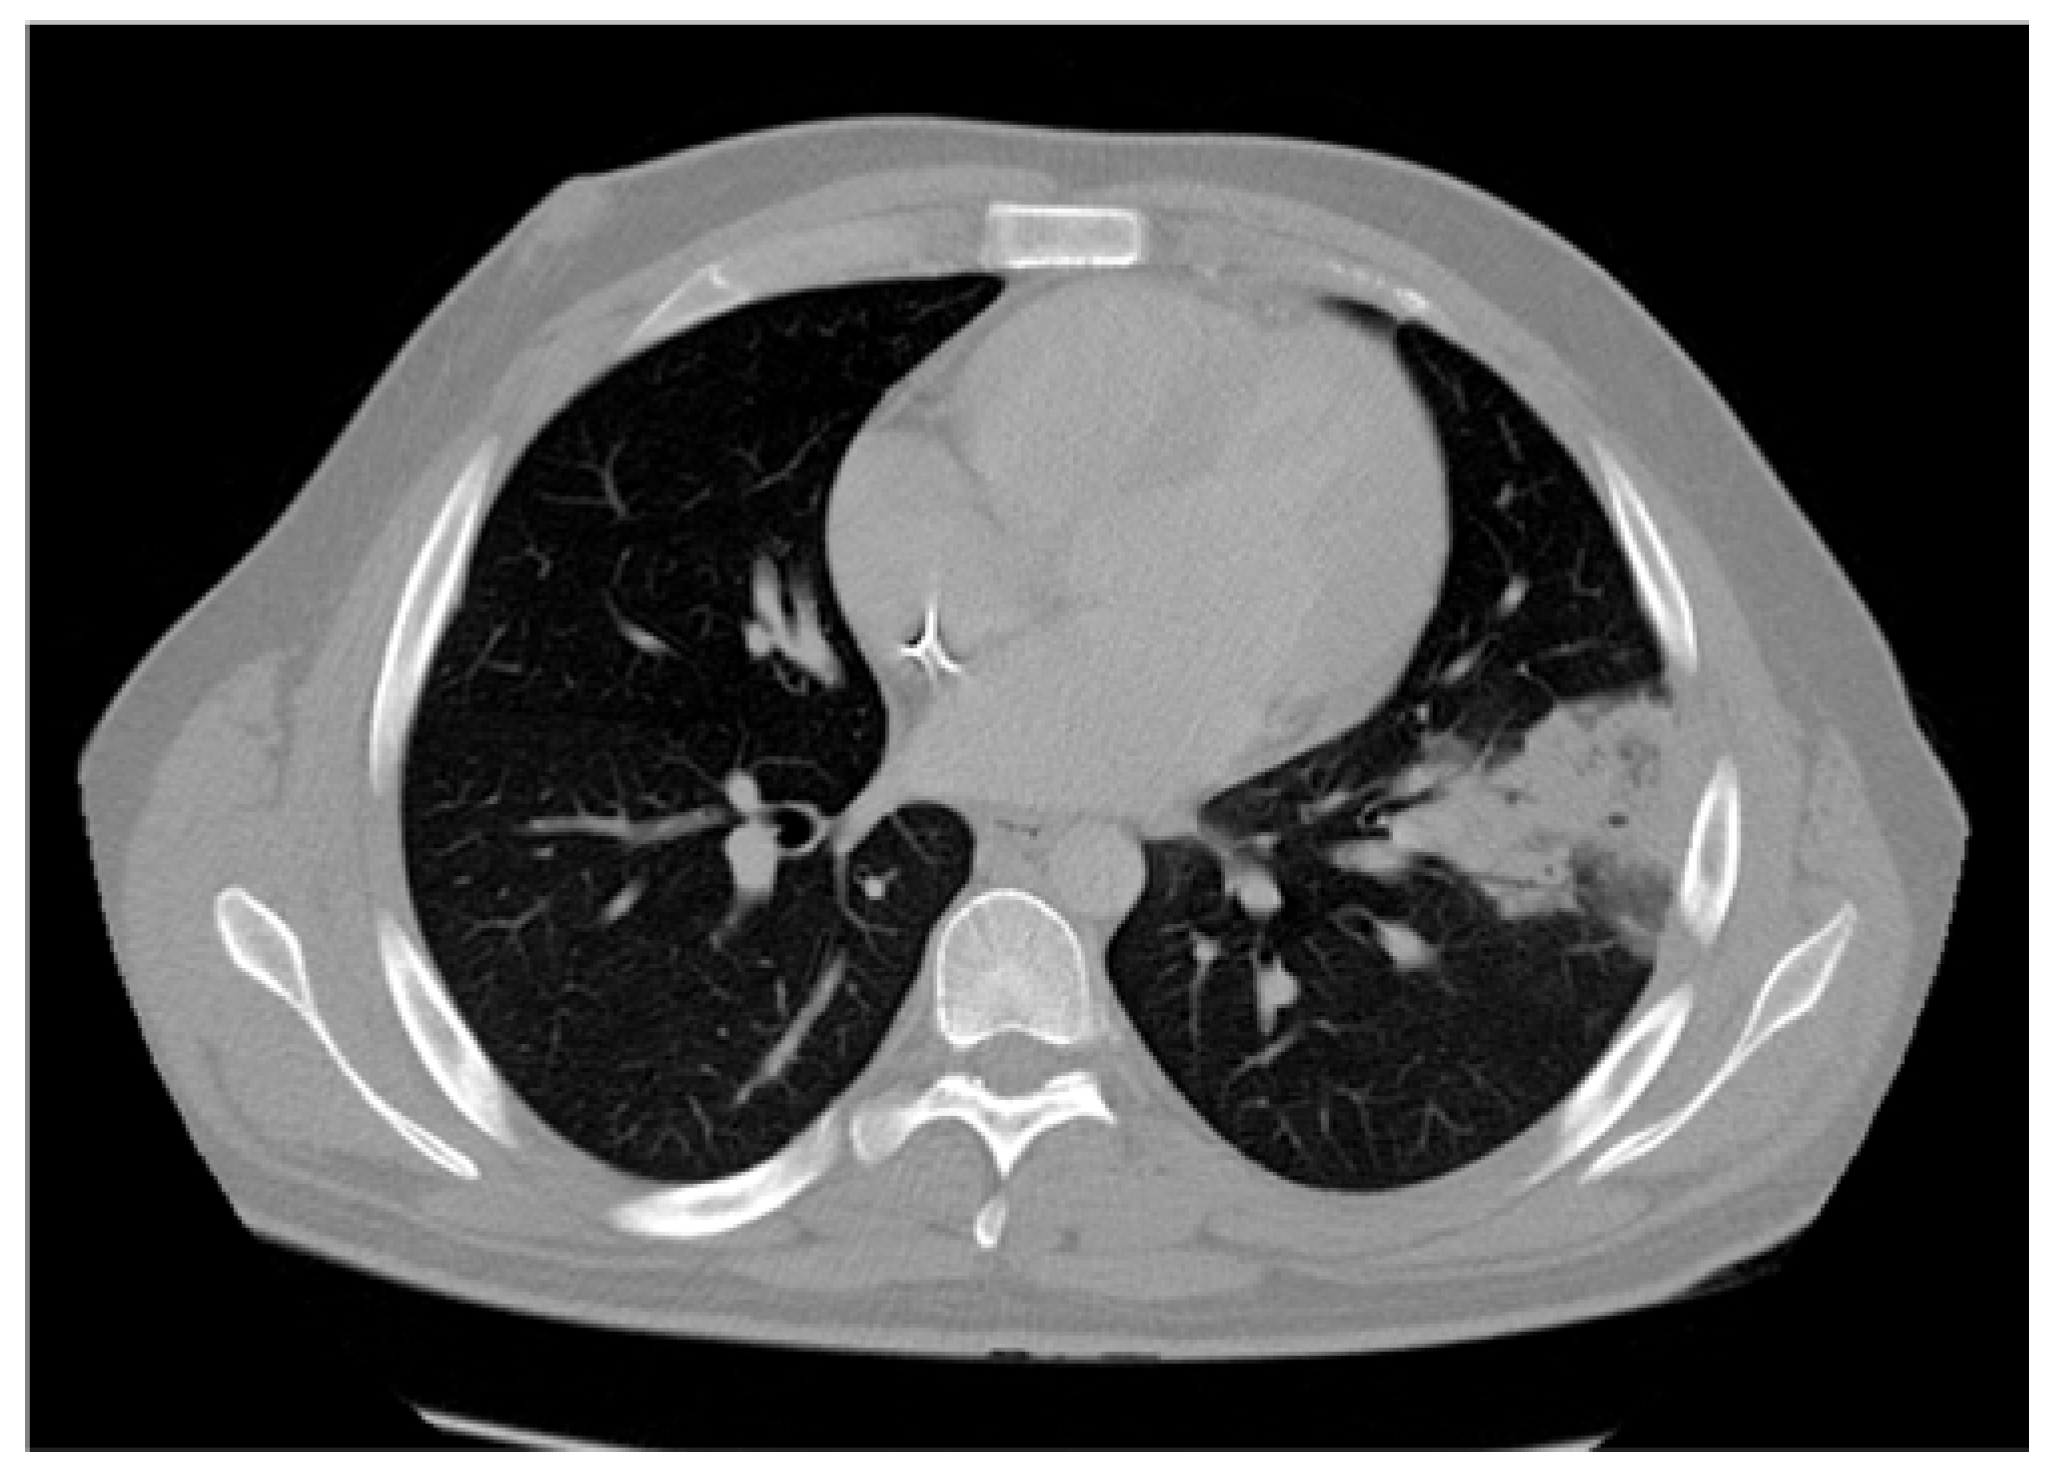

Case presentation